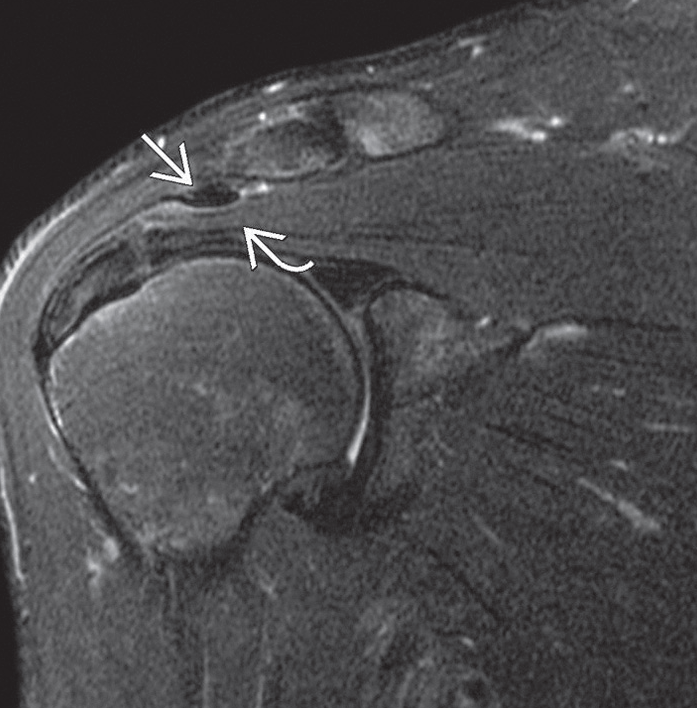

| A. Supraspinatus tendonunun korakoakromial bağ ile ilişkisi, B. Supraspinatus tendonunun sıkışmasını gösteren MR görüntüsü | |

Bazen film teşhis için yeterli olmayabilir. Bu durumda MR çekilebilir. MR’da bursa içinde sıvı ve tendonlarda inflamasyon hali görülür. Bazen de omzun döndürücü tendonlarında yırtık görülebilir.Teşhis amaçlı olarak bursa içine yerel uyuşturucu ilaç verilebilir. Bu enjeksiyon sonucu ağrı geçerse teşhis doğrulanmış olur.